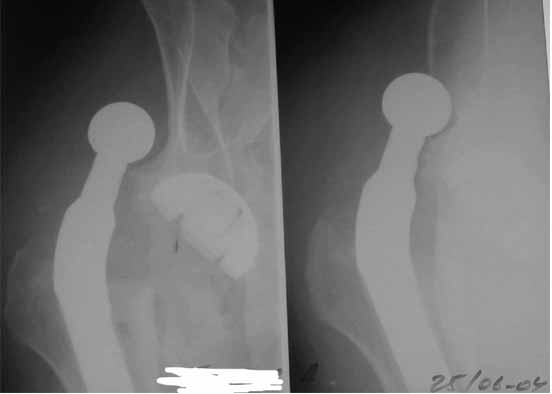

Я думал, это не очень важно. Вышлю и во время вывиха. Я просто не успел отснять их, а товарищ мой немного торопил - волнуется.

Во вложении - рентгенограммы после вывиха и после вправления.

Конечно, чудеса бывают, давай попробуем поиграть в эти игры, учитывая характерологические особенности нашего общего знакомого.

Идея очень простая, в случае, если удасться прожить без вывиха 2.5-3 месяца, вероятность его возникновения в будущем значительно уменьшится. Оптимальный вариант - повторная иммобилизация на срок 6 недель с нагрузкой на ногу (как бы я ни не любил гипс, но этот путь проверенный и может дать результат). Если это невозможно, то исключительно осторожная реабилитация под строгим контролем без резких движений (спать в положении на спине с отведением и подушкой под коленкой и т.д.). Ходьба сама по себе не опасна, опасен переход от положения "лежа" в положение "полусидя" и "стоя" и наоборот.